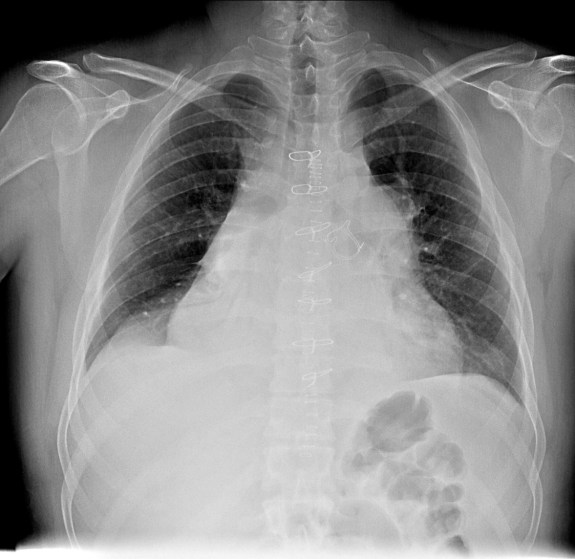

CASO: Operada de esofaguectomia y reconstrucción con coloplastia hace 3 meses. Sintomas de neumonía.

Hallazgos:

- De inicio llama la atención una densidad practicamente total del todo el hemitórax izquierdo, lo cual podría hacernos pensar que estamos ante una posible neumonía.

- Sin embargo el tórax está no está bien centrado, observar como la clavícula izquierda se encuentra casi en la mitad del pulmón, por tanto lo que vemos blanco es el mediastino ya que el tórax está rotado.

CENTRAJE:

El correcto centraje se determina comprobando que las extremidades internas de ambas clavículas equidistan de las apófisis espinosas vertebrales.

Mismo paciente, al cual esta vez se le ha tomado una radiografía en PA y en sedestación. Observar como las clavículas están equidistantes a las apófisis espinosas y como ha desaparecido el velamiento del pulmón izquierdo.

Por otra parte, paciente presenta una cardiomegalia y un discreto ensanchamiento del mediastino es probable relación con cambios postquirúrgicos.